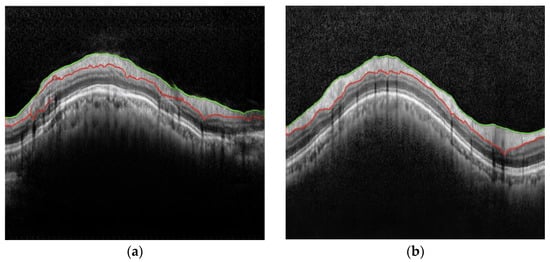

3.2. Image Conversion Result

Figure 2 shows one of the A-raw and B-curve images used in the test stage, while Figure 3 presents the B ^ -curves by transforming the A-raw image using the pix2pix and cycle-GAN methods, respectively. When compared to the actual B-curve image data, the pix2pix method struggled to produce accurate images. Due to the semi-paired images not aligning perfectly at the pixel level, pix2pix generated outputs with several overlapping ghost images. In contrast, cycle-GAN was able to generate B ^ -curve images that more closely resembled the B-curve.

Figure 2. Images of A-raw and B-curve. (a) A-raw; (b) B-curve. The colored lines are the manual segmentation lines by clinical experts.

Figure 3. Predicted B ^ -curve images by transforming the A-raw image. (a) Pix2pix; (b) cycle-GAN. The colored lines are the segmentation lines generated by each method.